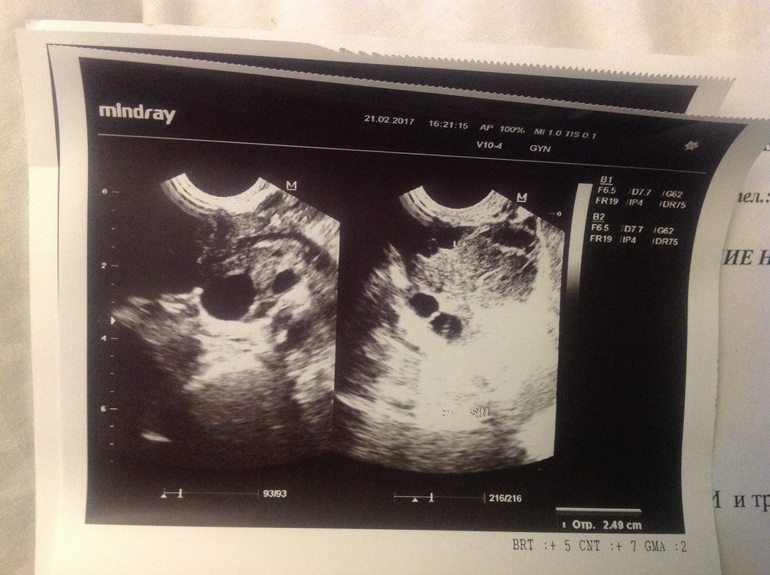

Фоликулометрия на 21ДЦ

ФолликулометрияВрач мне сказала что О не будет в этом цикле,но тесты говорили другое и решила я сходить проверить это,и что,была О,да ещё и какая,сказала всё хорошо,ЖТ (мощное какое говрит) 25 мм,эндометрий хороший очень сказала,говорит дай бог что бы получилось ,спросила,а когда примерно О была,она сказала что прмерно только,была 16-17 ДЦ,но тогда были и тэсты полож.,хз короче когда она была,ПА был один раз на 14ДЦ,посмотрим что из этого получится

Эндометрий 11мм гиперэхогенный с четкими контурами.

Позадиматочно - свободная жидкость.

В левом яичнике лоц-ся желтое тело d 25мм.

Эхографические признаки второй фазы менструального цикла.